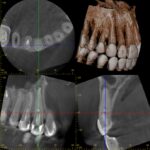

他院にて左上2番に被せ物(セラミック)を入れたが作り変えても何度も外れてしまい、 セカンドオピニオンで当院に来院。初診時は既に外れている状態でした。 ※レントゲン撮影時は外れた被せ物を入れて撮影しています。

パノラマレントゲン、CTを撮影したところ破折(ひび割れ)があることが分かりました。 唇側に破折線がありそちらだけ骨が吸収しているのが分かります。(写真①) これでは被せ物(セラミック)を入れてもすぐに外れてしまうのは当然です。 残念ながら破折の場合はヒビや割れの位置によりますが、抜歯の適用となります。 この方も奥まで破折線が入っていた為抜歯となります。